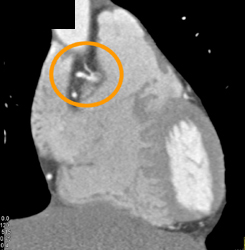

Diagnosis

Normal RCA